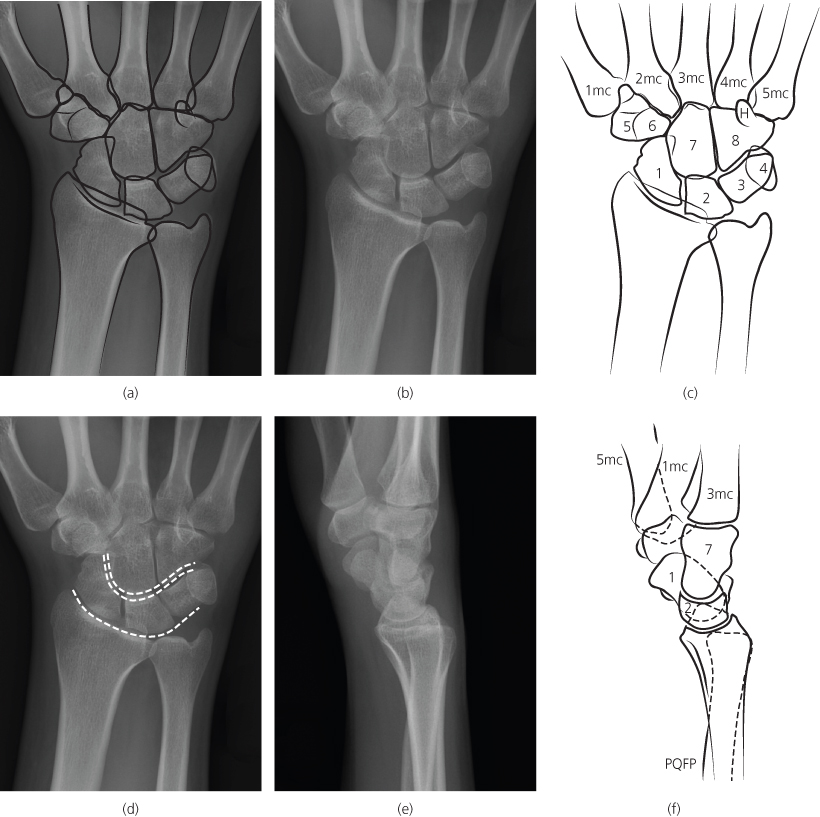

x ray of right hand and wrist

Posts: x ray of right hand and wrist